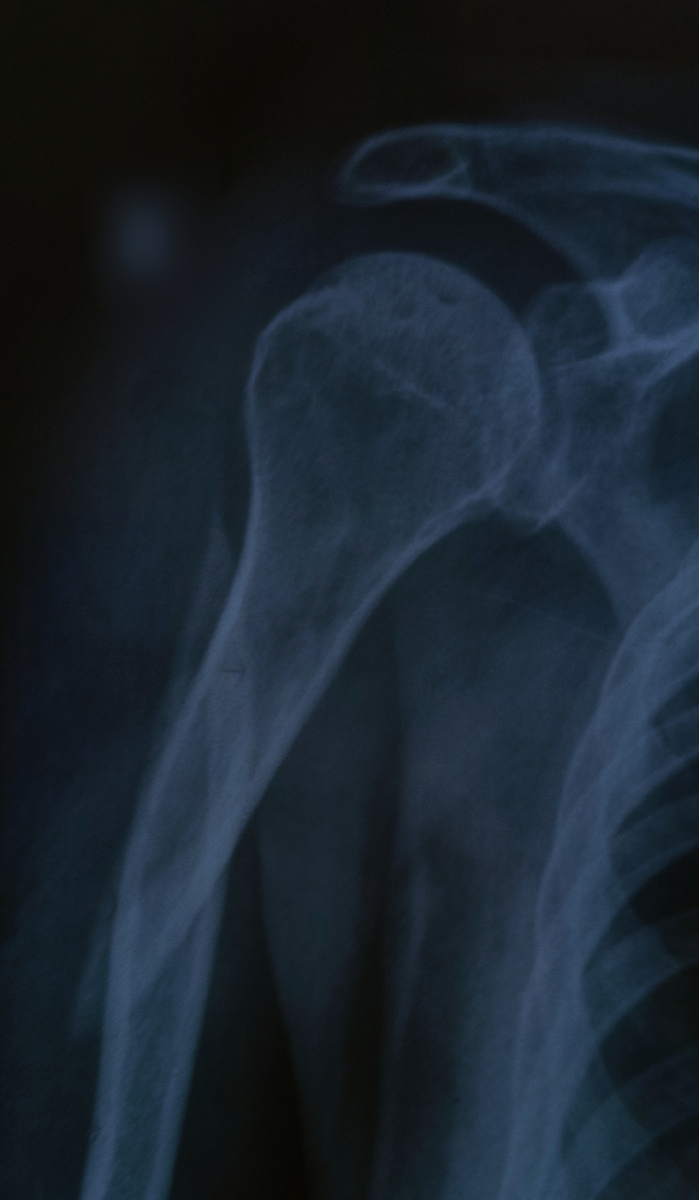

Мужчина пришел, 48 лет, на снимок плечевой кости. Вид очень помятый, как в плане одежды, так и лица.

–И где же вы так ударились? –ставя в нужное положение спросила я, чувствуя, что маска на лице от запаха не спасает.

–Где-где! Дома, по пьяни упал, на тумбочку прямо.

–Позавчера, ночью, –уточнил он.

–Да куда там сразу! Во-первых, я сразу и не понял, а во-вторых, постеснялся. Дай, думаю, маленько отлежусь, чтобы врачей не смущать своим состоянием.

Ну , да , сломал так неплохо. Если не откажется, то конструкцией на ближайшее время в плечевой кости обеспечен. Пока КВОТ полно, начало года же)